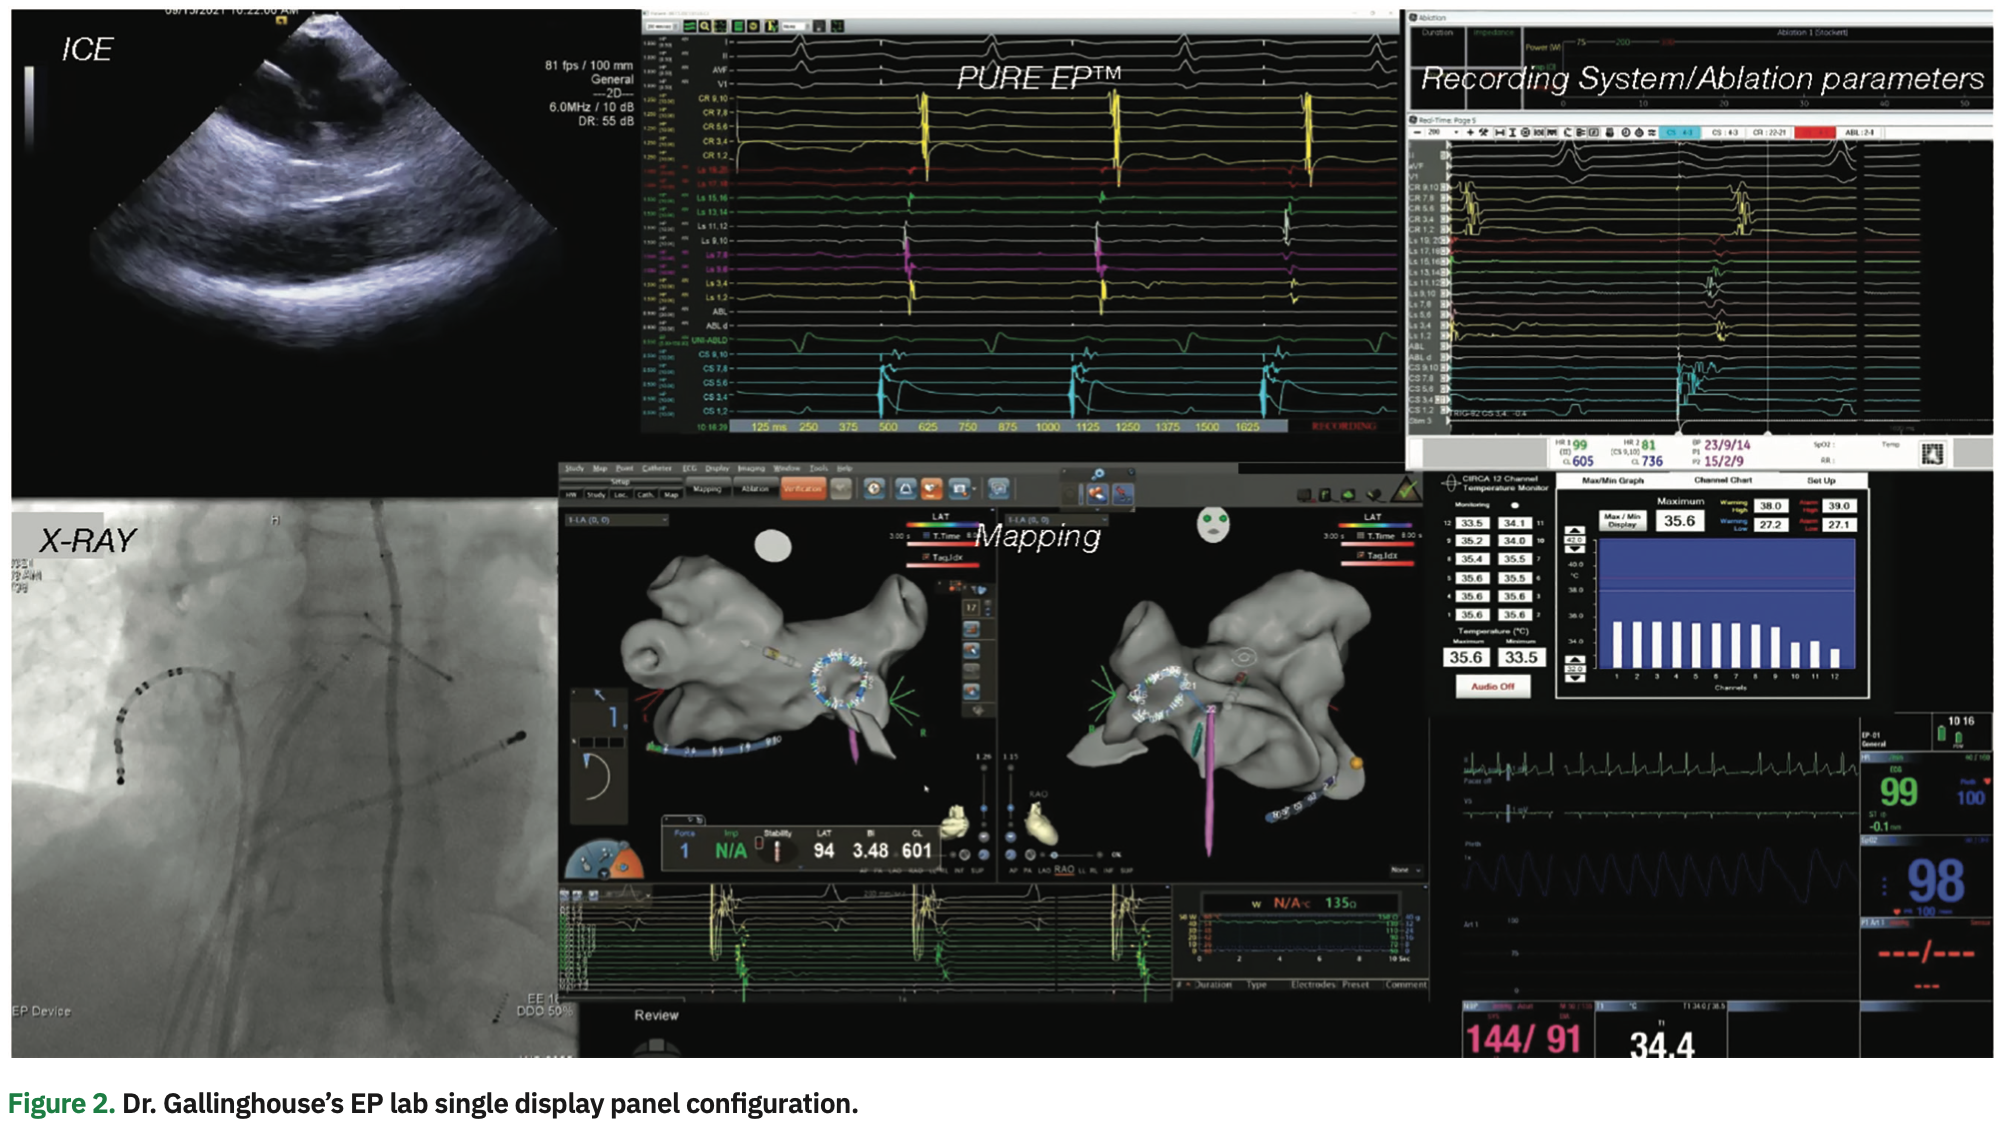

We’ve made PURE EP™ signals central to our workflow, and it has become the primary source of physiologic signal information. For our setup, we have visualization of two screens: the PURE EP Live window and the 3D mapping window. Since it is essential to clearly discern small, fractionated signal potentials to effectively treat complex arrhythmia substrates, the focus is on the PURE EP window. We enhance the 3D map by tagging small, fractionated signals seen on PURE EP™, which we consider critical to the case. Overall, PURE EP™ enhances our interpretation of the 3D map and allows more precise treatment of ablation targets.